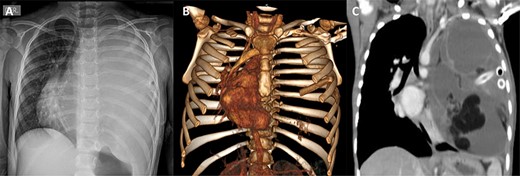

(A) Preoperative chest X-ray showing total atelectasis of the left lung and deviation of the cardiac silhouette to the right. (B) CT scan showing deviation of the cardiac silhouette to the right. (C) Heterogenic density tumor multiloculated of the left hemithorax, which probably originated in the mediastinum and extended to the whole left pleural space with displacement of the mediastinum to the right

A 4-year-old female with complete vaccines and without prior pathological prenatal history was admitted and transferred with a diagnosis of pleural effusion from a primary health center where a thoracic drainage tube was placed. She presented a 1-month history of progressive cough, fever and dyspnea. The physical exam was relevant for thoracic asymmetry, diminished breath sounds and vocal vibrations in the left hemithorax. A chest X-ray showed a total occlusion of the left hemithorax with deviation of the mediastinum to the right side. A computed tomography (CT) scan showed pectus excavatum and the presence of a large multiloculated mediastinal mass extending to the left pleural space (Fig. 1). The mass was heterogeneous containing soft tissue elements, cystic areas and calcification. Laboratory workup was remarkable for mild anemia (hemoglobin 10.2 g/dl), eosinophilia (5.2 cells × 109/l) and elevated alkaline phosphatase. α-Fetoprotein (AFP) and β-human chorionic gonadotropin (β-hCG) were both normal; cancer antigen-125 (CA-125) was elevated (83.3 UI/ml, normal <46 U/ml). Initial assessment suggested benign teratoma.